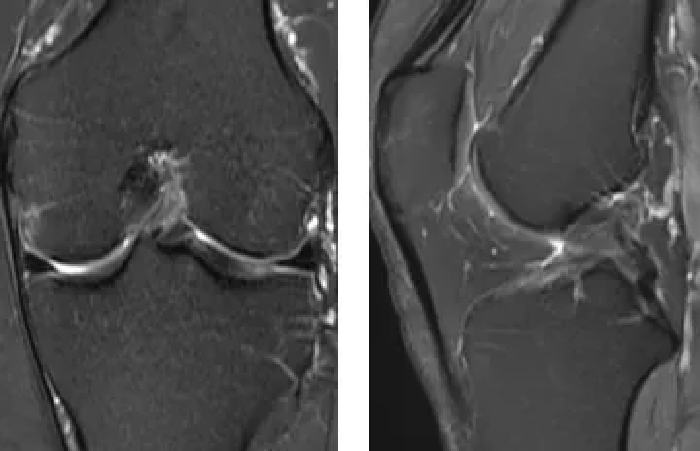

术前MRI提示:

左膝前交叉韧带损伤,左膝内外侧半月板损伤